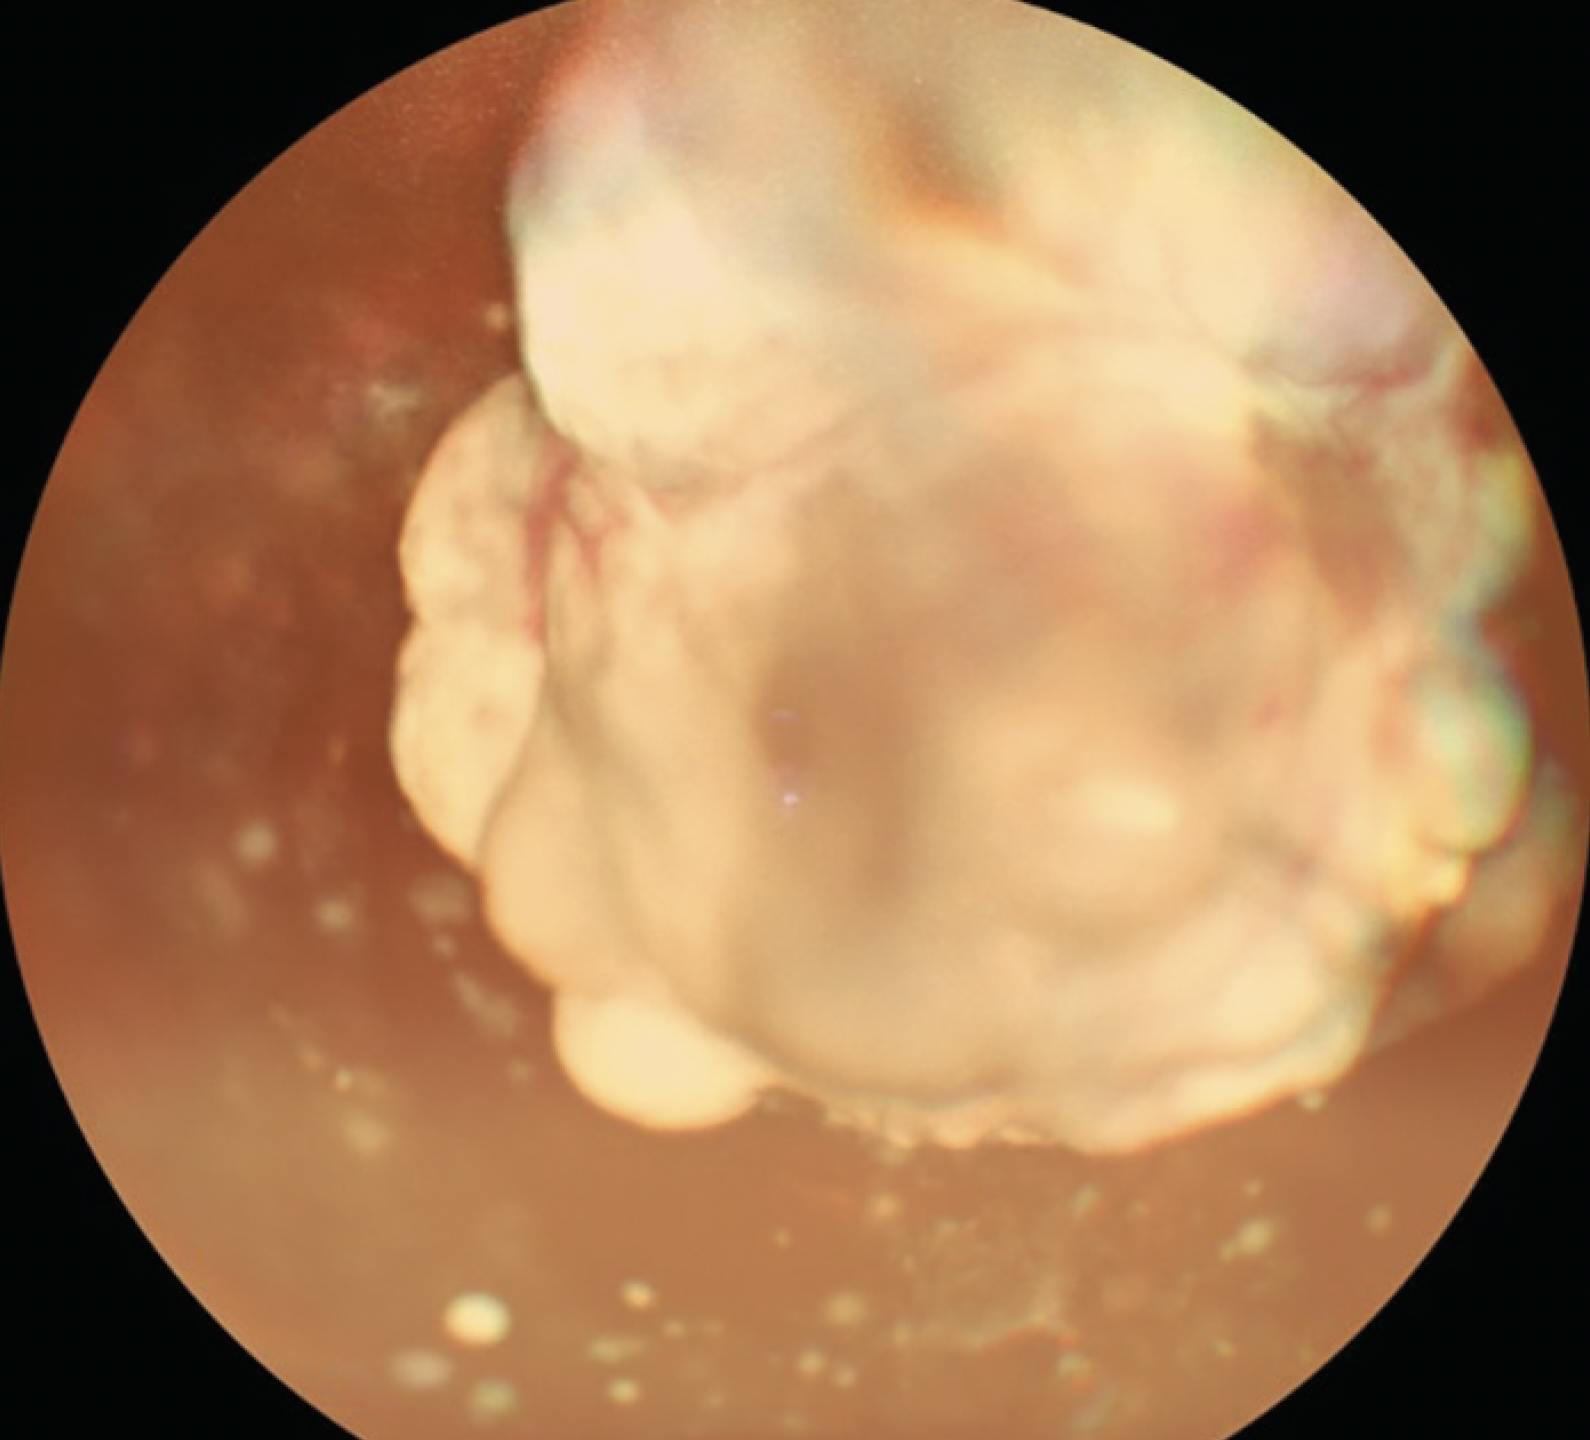

A 2.5-year-old girl presented with dim vision and whitish reflex in the right eye for 2 months. Dilated fundus examination of the right eye revealed multiple whitish nodular masses with vitreous seeding, indicative of retinoblastoma (Figure 4). Ultrasound of the right eye revealed hyperechoic homogenous masses with high spikes and restricted movements suggestive of calcification associated with retinoblastoma. The patient underwent enucleation of the right eye.

<p>Figure 4. Widefield color imaging of the right eye shows multiple whitish nodular masses with vitreous seeding associated with retinoblastoma.</p>

Figure 4. Widefield color imaging of the right eye shows multiple whitish nodular masses with vitreous seeding associated with retinoblastoma.